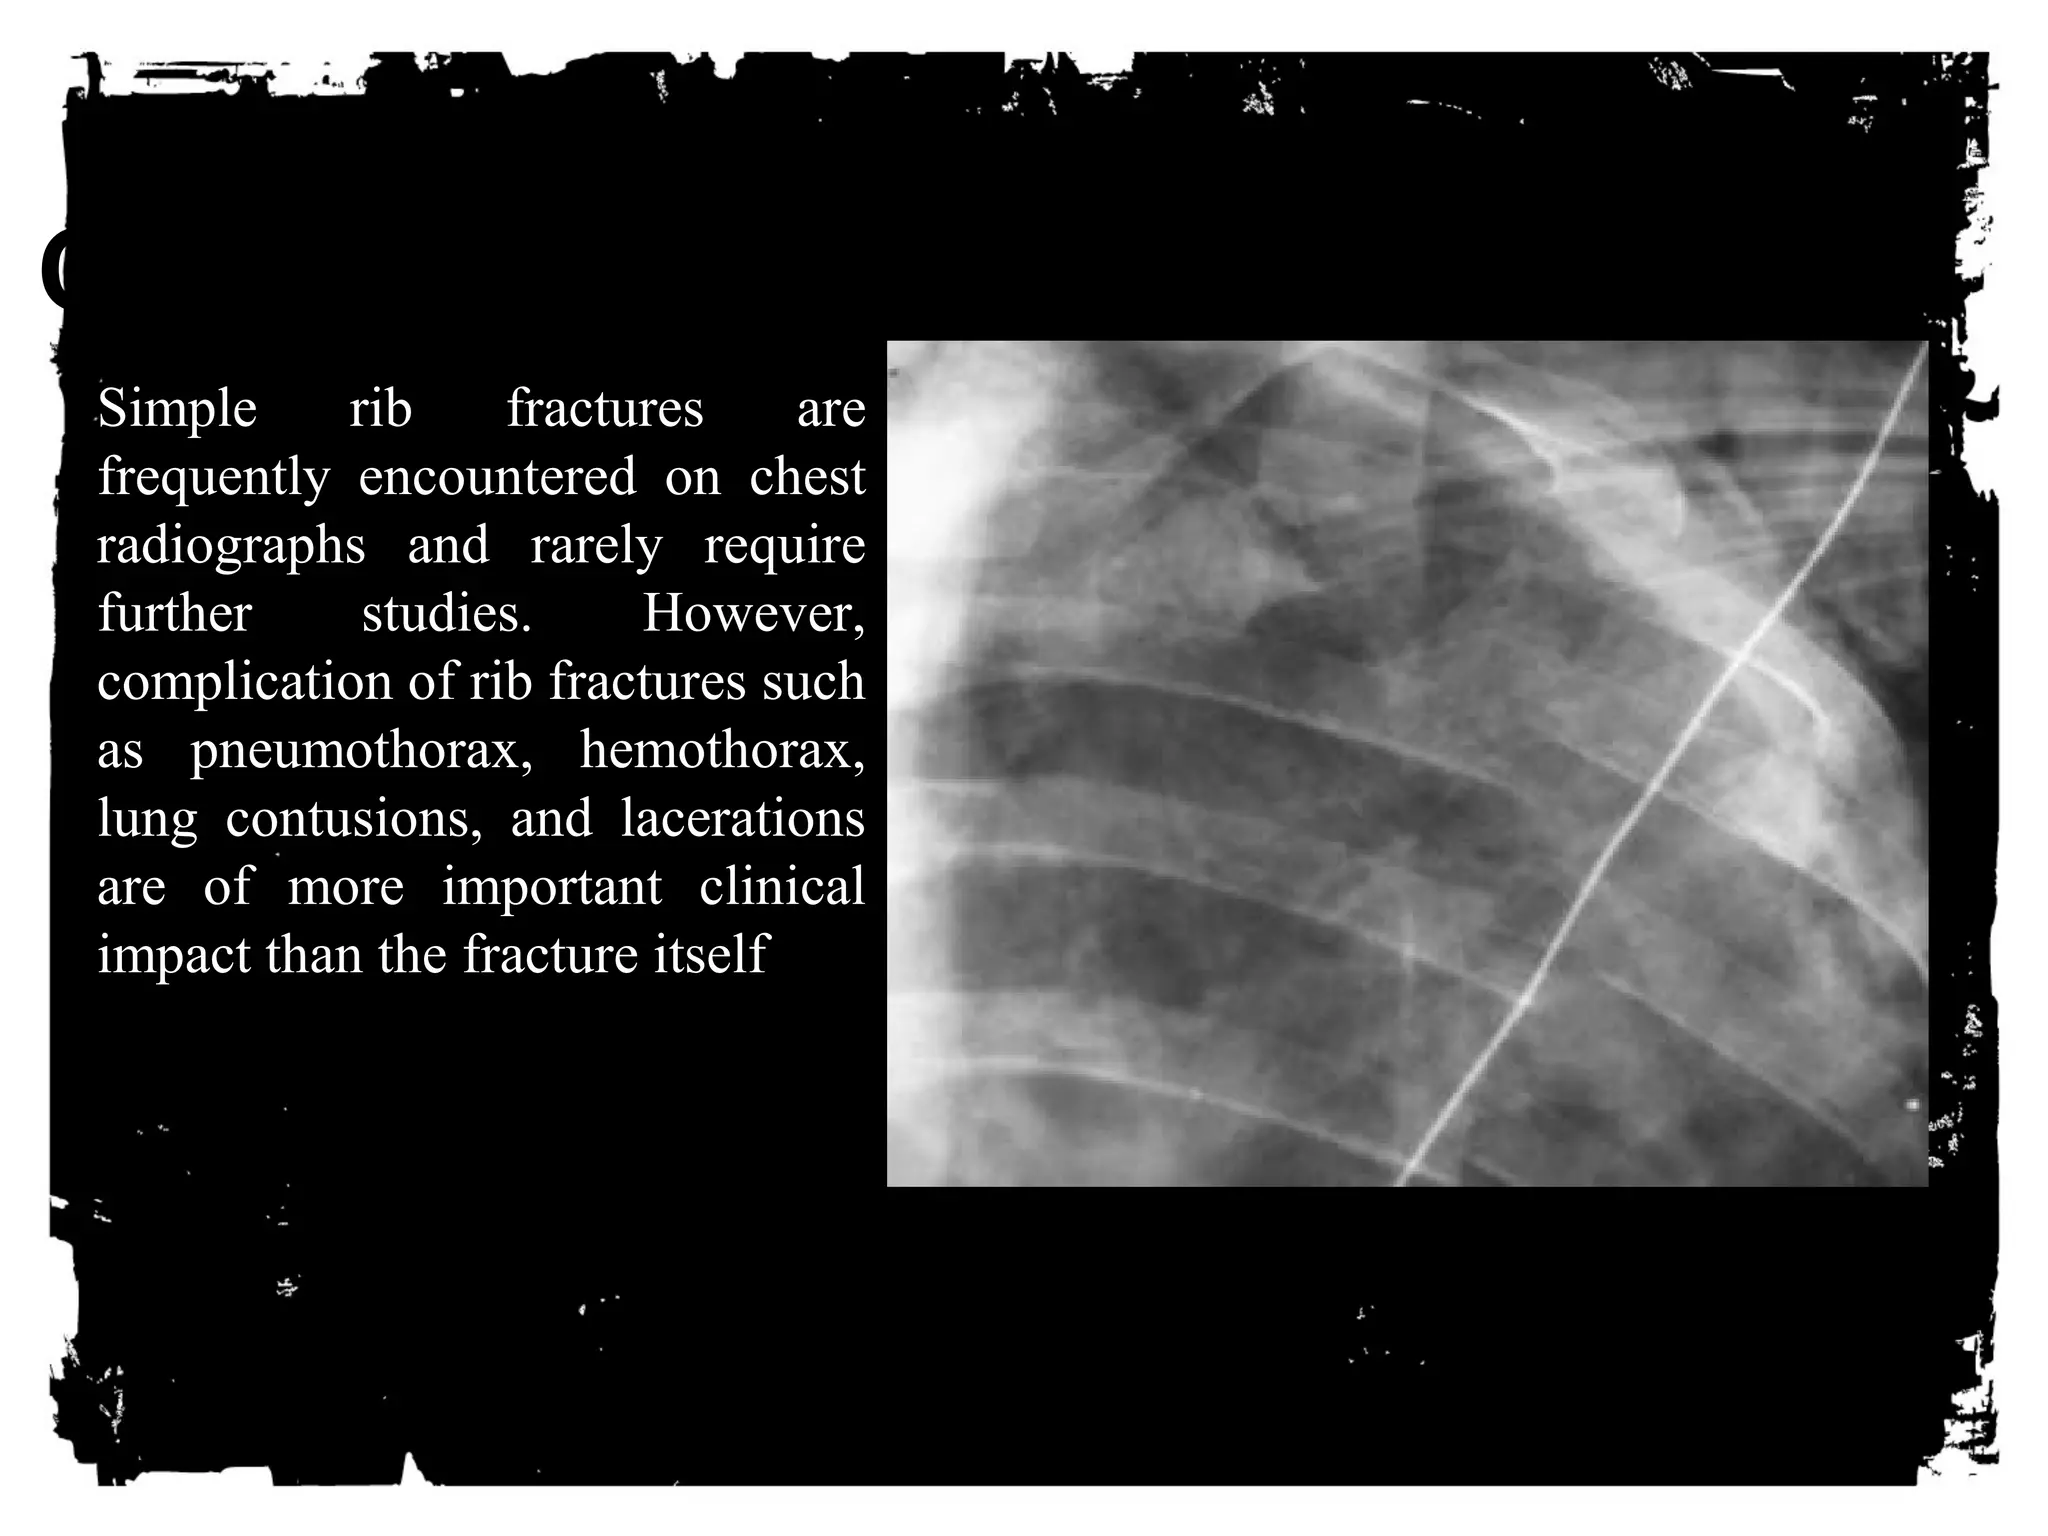

Simple rib fractures are

frequently encountered on chest

radiographs and rarely require

further studies. However,

complication of rib fractures such

as pneumothorax, hemothorax,

lung contusions, and lacerations

are of more important clinical

impact than the fracture itself